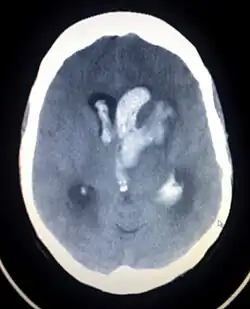

Intracerebrální krvácení

Intracerebrální krvácení způsobuje ložiskové intraparenchymové kolekce krve s expanzívním chováním.

- akutní traumatické hematomy – vznikají v okamžiku úrazu, patří do primárních mozkových poranění

- opožděné krvácení – s odstupem 6 hodin až několik týdnů po traumatu

Mezi klinický obraz patří v počátku krátké období zmatenosti či ztráta vědomí, dále dle lokalizace, velikosti hematomu a rychlosti zvětšování. Mezi diagnostické metody patří CT. Léčba je konzervativní (péče o vnitřní prostředí, antiedematózní léčba), případně neurochirurgické odstranění. Prognóza závisí na lokalizaci a rozsahu krvácení, obvykle zůstává ložiskový neurologický deficit.[2]